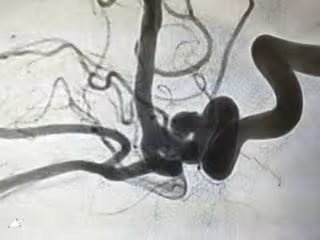

Imágenes de la intervención, obtenidas mediante angiografía con substracción digital donde se evidencia el antes y después del aneurisma cerebral tratado, totalmente ocluido tras la introducción del nuevo dispostivo.

Imágenes de la intervención, obtenidas mediante angiografía con substracción digital donde se evidencia el antes y después del aneurisma cerebral tratado, totalmente ocluido tras la introducción del nuevo dispostivo. - HOSPITAL UNIVERSITARIO FUNDACIÓN JIMÉNEZ DÍAZ